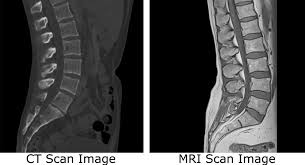

CT촬영 MRI촬영

CT검사는 인체에 X선을 투과, 횡단면상 단층으로 영상을 획득해 진단에 이용한다고 한다. 주로 뼈 등 단단한 조직 내부 확인을 위해 사용되며, 우리 몸 대부분 장기는 CT로 확인할 수 있다고 한다.

X-ray 검사에서 이상 소견이 보였을 때 추가로 진행하는 CT 검사는 10~15분 정도로 1시간 이상 시간이 소요되는 MRI에 비해 검사 시간이 짧다. 또한 밀폐된 공간에서 하는 검사가 아니기 때문에 폐쇄공포증 환자도 무리 없이 검사를 받을 수 있고 뼈 질환과 척추관 협착증은 오히려 MRI 보다 선명한 결과를 확인할 수 있어 뼈의 골절 유무 확인은 주로 CT 검사를 시행한다고 한다.

그러나 MRI는 CT에 비해 출혈, 골절 등의 병변이 잘 보이지 않는 경향이 있어 응급상황에서는 최초 검사로 CT를 우선 시행하는 경우가 많고 세밀한 판독을 위한 추가 정밀검사 방법으로 MRI를 시행하게 된다고 한다. 한편 MRI는 근육파열, 신경손상 등을 확인하는데 효과적이고 특히 디스크 판독에도 탁월하다고 한다.